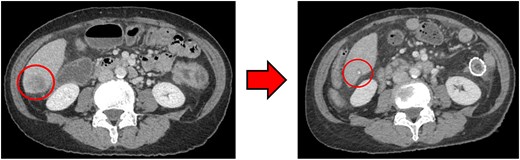

Computed tomography (CT) revealed wall thickening of the descending colon with increased pericolic fat tissue density (Fig. 2). Multiple enlarged regional lymph nodes were observed. Liver metastases were identified in the liver S5/7 and S6 (Figs 3 and 4). The S5/7 lesion was located near the anterior branch of the portal vein and the right hepatic vein.

(Left: Before NAC) Liver metastasis in the liver S6. (Right: After NAC) Liver metastasis in the liver S6. It had decreased substantially, with near-complete necrosis.

After four cycles, CT revealed significant shrinkage of the primary lesion (Fig. 2), disappearance of lymph node metastases, and complete resolution of the S5/7 liver metastasis (Fig. 3). The S6 lesion had decreased substantially, with near-complete necrosis (Fig. 4). Tumor markers declined (CEA 16.7 ng/mL, CA19–9 31.1 U/mL).